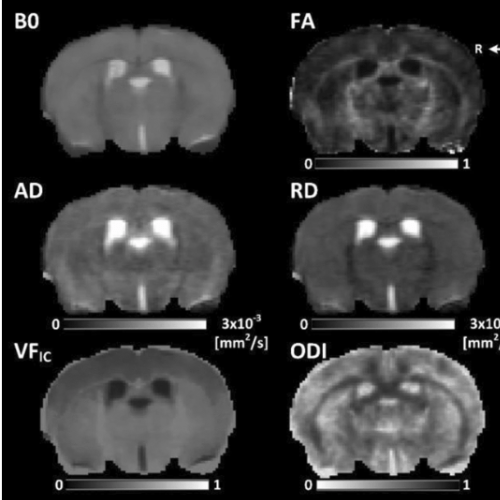

Alterations of brain microstructures in mouse model

Images of six brain scans over black background.

Read Article